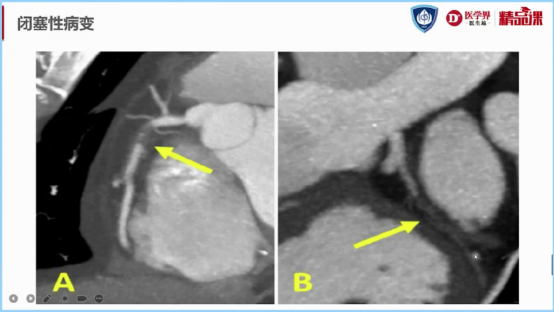

图10:闭塞示意图

CTA图像,百闻不如一见。但由于篇幅原因,今天小界就先说到这啦!在接下来的内容中,黄浙勇教授还对CTA图像中次全闭塞和完全闭塞鉴别、斑块性质、伪影的解读判断(排除假阳性)进行了详细讲授。